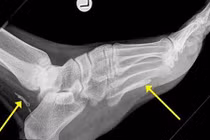

Lúc này, vào viện xét nghiệm máu thì các bác sĩ cho biết em bị mắc ung thư bạch cầu, chỉ chậm vài ngày là em có thể tử vong. Olivia phải cọc hết tóc và điều trị hóa trị. Các bác sĩ cho biết, xương của Olivia quá yếu và không bao giờ có thể đi lại được nữa.